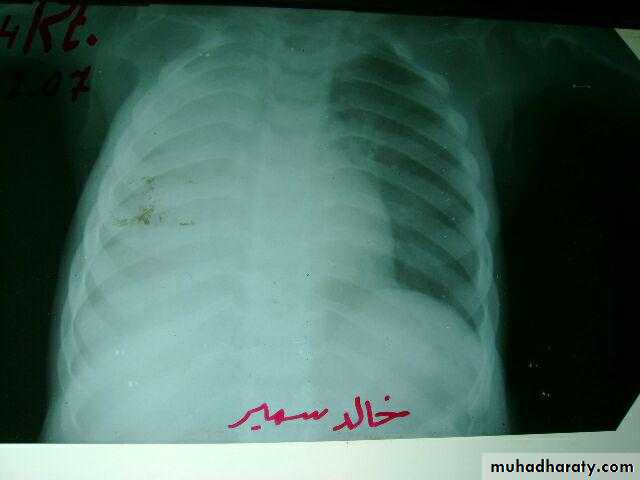

3 month infant presented with cough & dyspnea

Xray shows hyperinflated chest (depresed diaphragm , > 6 ribsMay be bronchiolitis

Hyperinflated chest